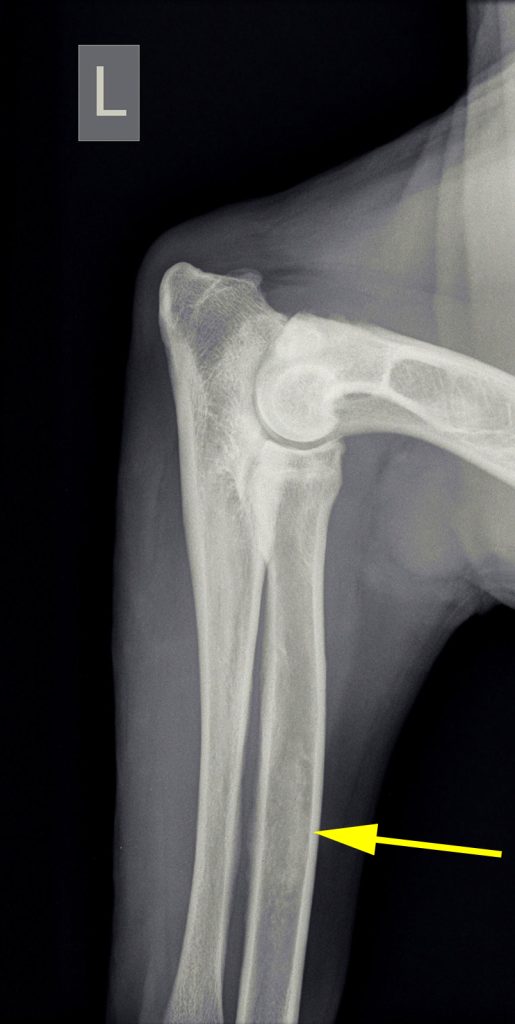

Op röntgenfoto’s kan groeipijn vaak zichtbaar gemaakt worden; het uit zich als wolkvorming in de mergholtes van de lange botten. De pijnlijkheid kan meestal met pijnstilling opgelost worden. Omdat het echter alle lange botten kan aantasten, wisselt de kreupelheid die hiermee gepaard gaat regelmatig van poot. Het kan dan ook voorkomen dat de kreupelheid in bijvoorbeeld de voorpoot overgaat, om na een maand in de achterpoot op te treden.